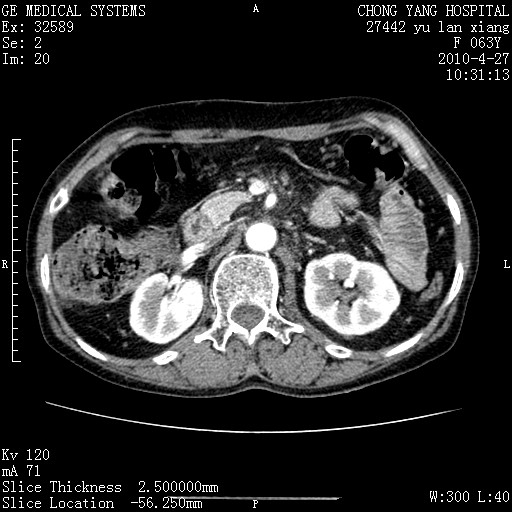

标题: CT26066:F63Y 上腹正中压痛半月,CA199:7400u/ml,MR示胰腺炎伴 [打印本页]

胰腺癌侵犯腹腔动脉干-分支、胃壁、左侧膈肌伴胰周及腹膜后淋巴结转移、胆囊切除术后。

胰腺癌侵犯腹腔动脉干-分支、胃壁、左侧膈肌伴胰周及腹膜后淋巴结转移、胆囊未显影。